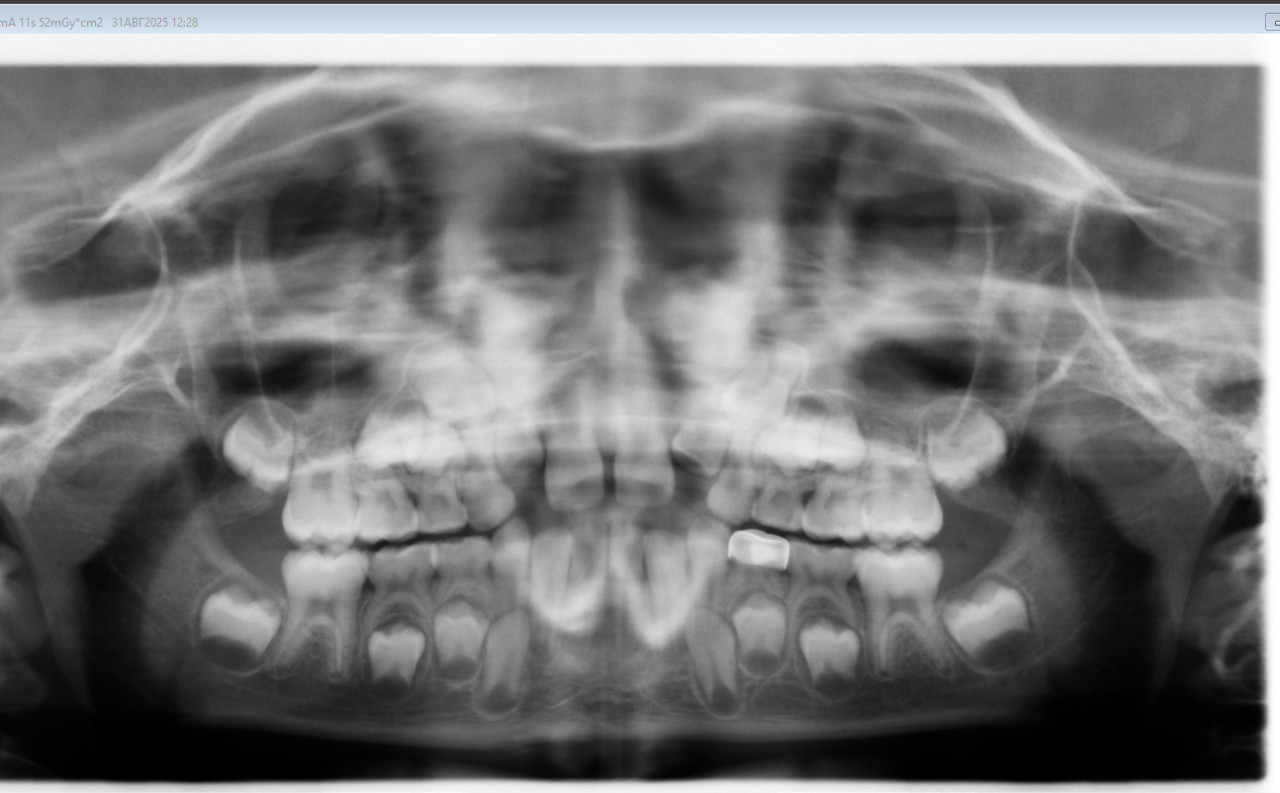

Снимок рентгена свежий сегодняшний. Были на консультации у ортодонта, нам сказали что последний аппарат сняли рано и что места нету для верхних зубов. Сказали необходимо ставить повторно аппарат Марка Росса примерно на 9 месяцев.

Вопрос к коллегам ортодонтам, исходя из снимка это действительно так, что повторно необходимо его ставить, тк места нет?

Здравствуйте. По рентген-снимку видно, что места для прорезывания постоянных верхних зубов действительно недостаточно и риск скученности остаётся. В таких случаях повторное применение расширяющего аппарата (в том числе аппарата Марка Росса) это стандартная тактика для создания пространства. Сроки ношения обычно подбираются индивидуально поэтому решение о снятии в прошлый раз вероятно было преждевременным. На данном этапе повторная установка аппарата оправдана, чтобы избежать выраженной скученности и более сложного ортодонтического лечения в будущем.

Здравствуйте.  На снимке действительно видно ограниченное пространство для прорезывания постоянных зубов, поэтому врач рекомендующий повторную установку аппарата принял правильное решение. Иногда аппарат снимают раньше по разным причинам (индивидуальная переносимость, состояние зубов или дёсен, решение семьи). Сейчас важно не акцентироваться на прошлом, а оценить актуальное состояние: при недостатке места расширение верхней челюсти поможет предотвратить выраженную скученность и уменьшить объём будущего лечения брекетами.